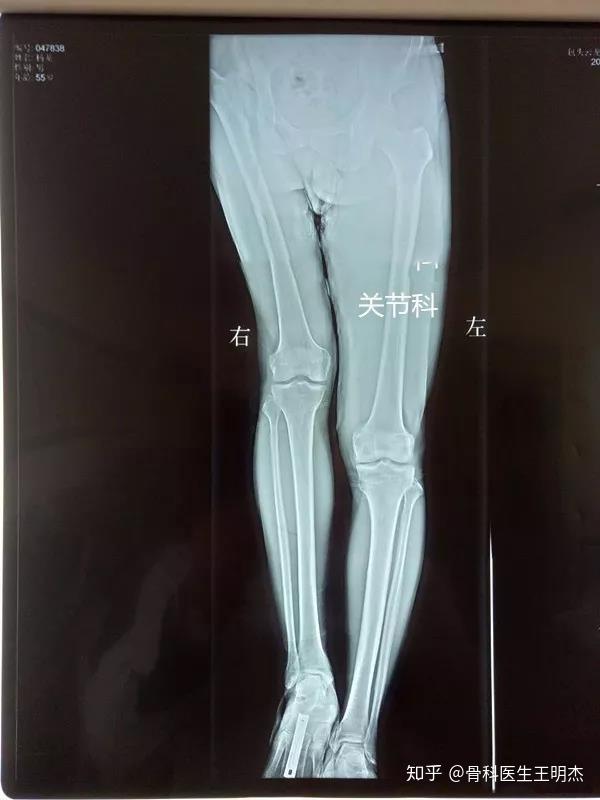

长短腿的定义

长短腿是怎么回事常见的7种原因一文详解附上训练教程

lld)是指人体下肢长短不齐,它分为结构性长短腿(anatomical lld)和

"长短腿"可以分为结构性(真性)和功能性(假性)两大类,形成原因有很多